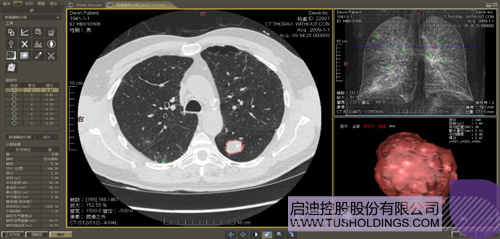

數(shù)字肺產(chǎn)品肺癌計算機輔助診斷

醫(yī)療影像智能分析是指運用人工智能技術、計算機視覺技術以及計算幾何技術對醫(yī)療影像進行自動分析,幫助醫(yī)生定位病癥、分析、跟蹤病情,并通過量化數(shù)據(jù)輔助醫(yī)生做出診斷,目前其旗艦產(chǎn)品“數(shù)字肺”已經(jīng)覆蓋多種肺部疾病的早期檢測、診斷、跟蹤、術前規(guī)劃等完整的醫(yī)療流程。在臨床實踐中,超過80%的醫(yī)療數(shù)據(jù)來自醫(yī)療影像,這些影像數(shù)據(jù)通常需要專業(yè)醫(yī)生進行解讀,工作的重復性高、效率偏低。如果能夠運用智能影像分析技術,同時結合臨床表現(xiàn)以及既往病例進行全面分析,那么就可以大幅度提升影像診斷效率和準確性,讓專業(yè)醫(yī)生的寶貴時間集中在復雜病情的診斷和治療等環(huán)節(jié)。